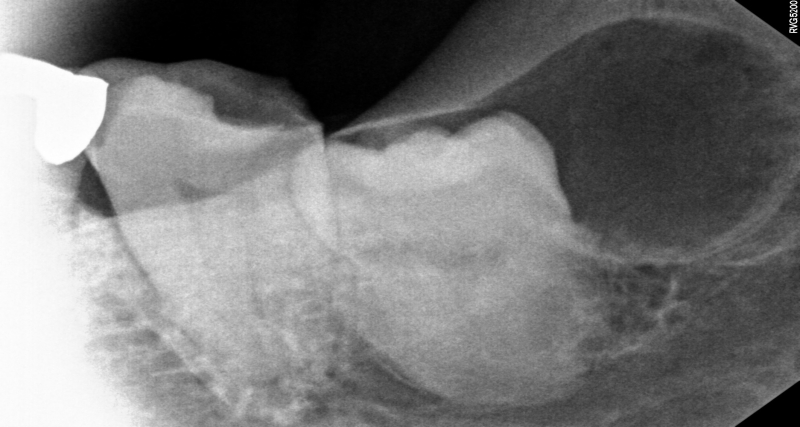

촬영일시: 2026.04.10